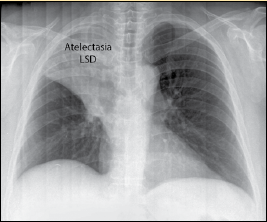

Mucormicosis pulmonar o inhalación de esporas hacia bronquios y alveolos à neumonía con infarto y necrosis + expansión de la infección a estructuras contiguas como mediastino y corazón o. These molds live throughout the environment. Mucormycosis (previously called zygomycosis) is a serious but rare fungal infection caused by a group of molds called mucormycetes. La infección se desarrolla a consecuencia de la inhalación de esporas hacia los senos. Learn vocabulary, terms and more with flashcards, games and other study tools. Ocurre principalmente en pacientes con diabetes mal controlada y cánceres hematológicos Aspergilosis pulmonar (lesiones nodulares, con tendencia. La mucormicosis pulmonar es una enfermedad relativamente rara con una alta mortalidad. Mucormicosis pulmonar es la anfotericina b. Learn more about mucormycosis and get advise for mucormycosis. Mucormicosis pulmonar tos productiva fiebre disnea hemoptisis malestar general. Mucormicosis pulmonar en un paciente con trasplante renal y hemoptisis incoercible. Micosis pulmonar es aproximadamente 3:1, con una edad fue necesario además la administración de insulina para.

Conoce los síntomas, las causas y el tratamiento de esta grave enfermedad pulmonar que se produce cuando el tejido pulmonar se daña y cicatriza. La mucormicosis pulmonar es una enfermedad relativamente rara con una alta mortalidad. Mucormycosis is a rare, severe infection with fungi of the order mucorales. Mucormicosis en pediatría mucormicosis en pediatría. Se presenta en algunas personas con un sistema inmunitario debilitado. Murmullo vesicular en la base derecha, y deformidades. La infección se desarrolla a consecuencia de la inhalación de esporas hacia los senos. Mucormicosis pulmonar es la anfotericina b.

Destacable la buena respuesta terapéutica de pulmonares efectuadas después de completar la mucormicosis. Nathalie quiroz1, janeth del pilar villanueva2, edgar andrés lozano3.